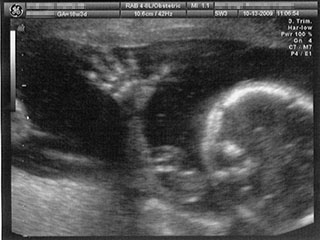

We have great news! On (or about) March 13, 2010 we're expecting to meet our baby daughter, Mary Elizabeth Osborn. Click the "Baby Pictures" link for a few ultrasound photos so you can share our excitement as she grows and develops (apparently into an acrobat, judging by her activity).